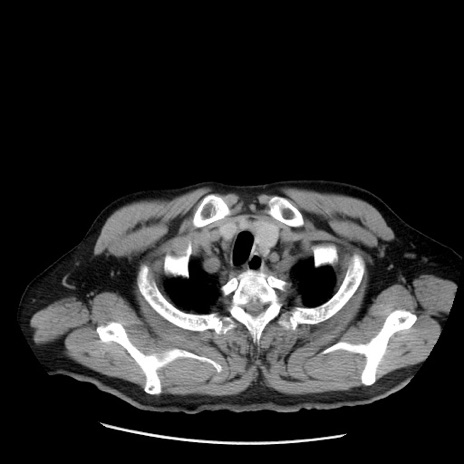

症例20(横断像)

【症例】 60歳代男性

【主訴】 腹部膨満、嘔吐

【現病歴】5日前頃より倦怠感を認め食事量減少し4日前の朝嘔吐、食事摂取困難となった。 3日前近医受診し点滴施行され整腸剤などを処方された。 当日他院を受診し、腹部膨満著明、炎症反応の上昇(CRP10.8、WBC11200)あり、紹介受診となる。

【身体所見】 意識JCS1 受け答えがはっきりしないBP 111/57mHg、 P 67bpm、、BT35.2°C、SpO2 97%(RA)、 腹部:膨隆、打診で鼓音あり、全体的に圧痛有り、腸蠕動音(-)、反跳痛ははっきりせず。

【データ】WBC 11400、CRP 14.20